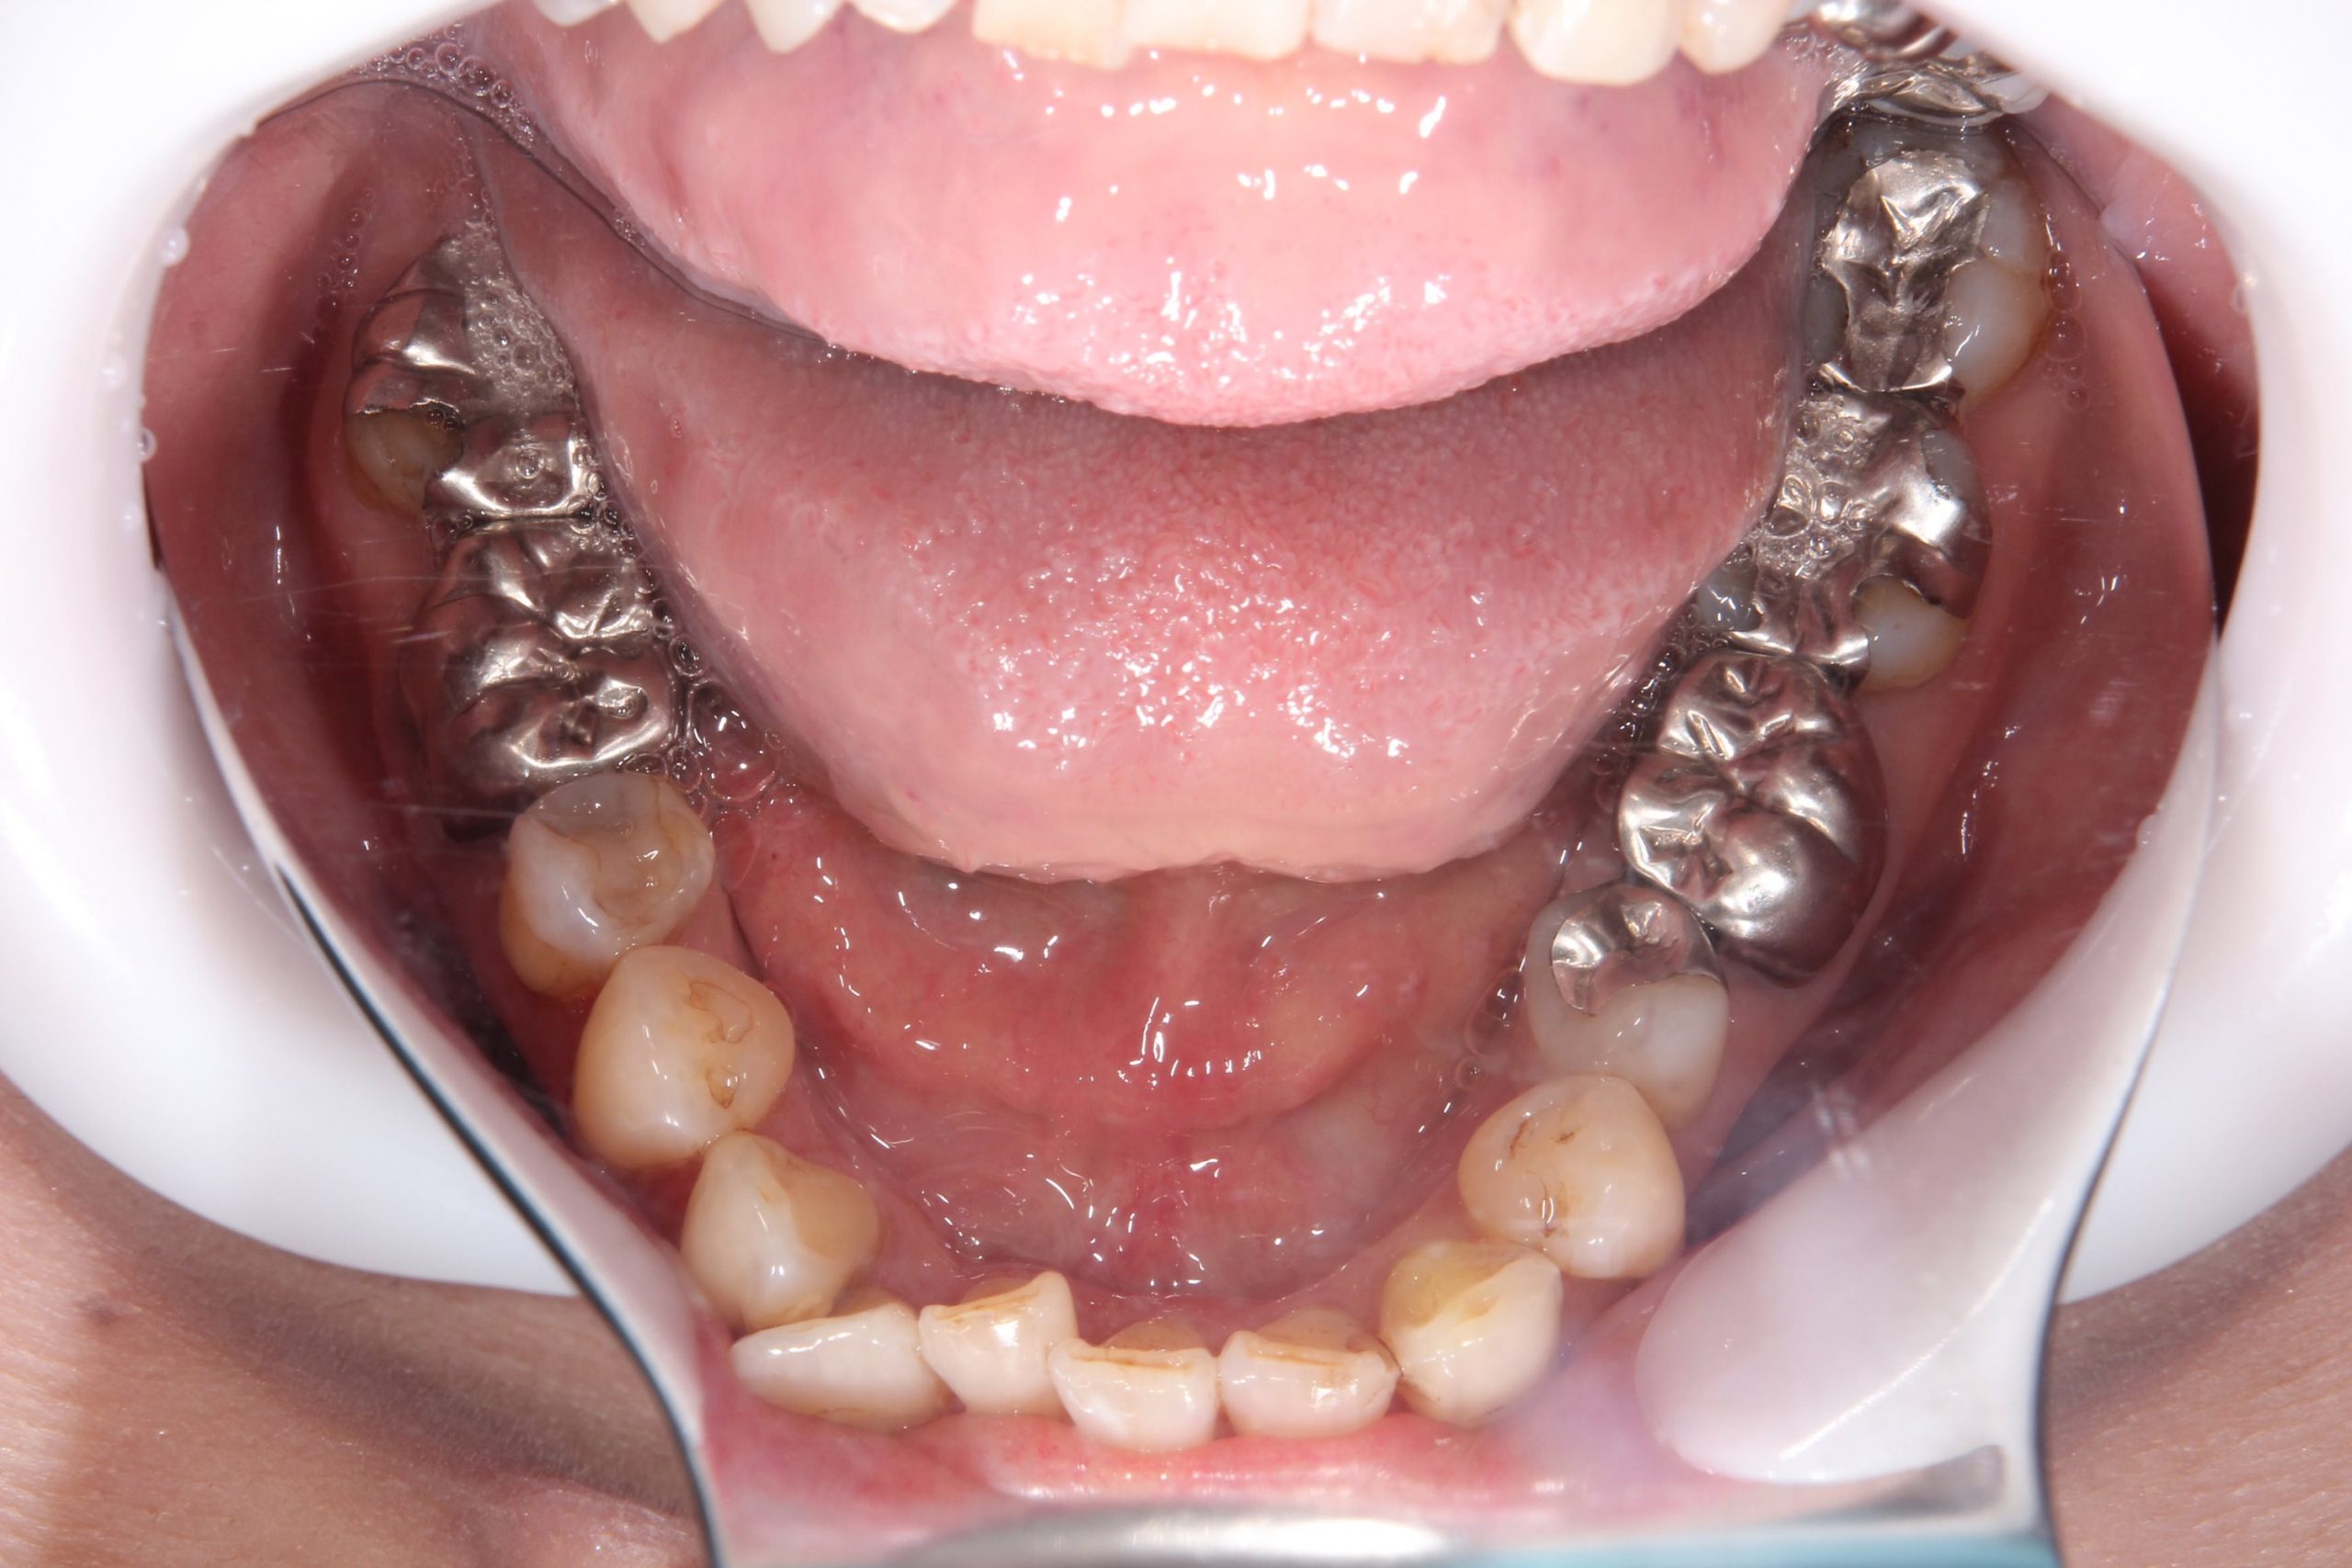

| 年齢 | 61歳 |

|---|---|

| 性別 | 女性 |

| 主訴と治療部位 | 金属の見た目が気になるので白くしたい。 右上4〜7番、右下6番、左上6.7番、左下5〜8番 |

| 治療内容 | 右上4・6・7番、左上6~7番、左下5・7・8番 セラミックインレー 右上5番、右下6番、左下6番 オールセラミッククラウン |

| 治療費 | 合計786,500円 セラミックインレー55,000円×8本 ファイバーコア(土台)16,500円×1本 オールセラミッククラウン110,000円×3本 (2022年12月現在) |

| 治療期間 | 1ヶ月 |

| リスク・副作用 | 噛み合わせが強い場合、割れたり欠けたりすることがある。 |

| 治療方針 | 咬合確立のため、左右に分けて回数を少なく計4回で行った。 |

| 担当者所見 | 前歯部が叢生なので前歯に負担がかかりすぎないように、臼歯部が左右均等に当たるように咬合調整を行った。 |